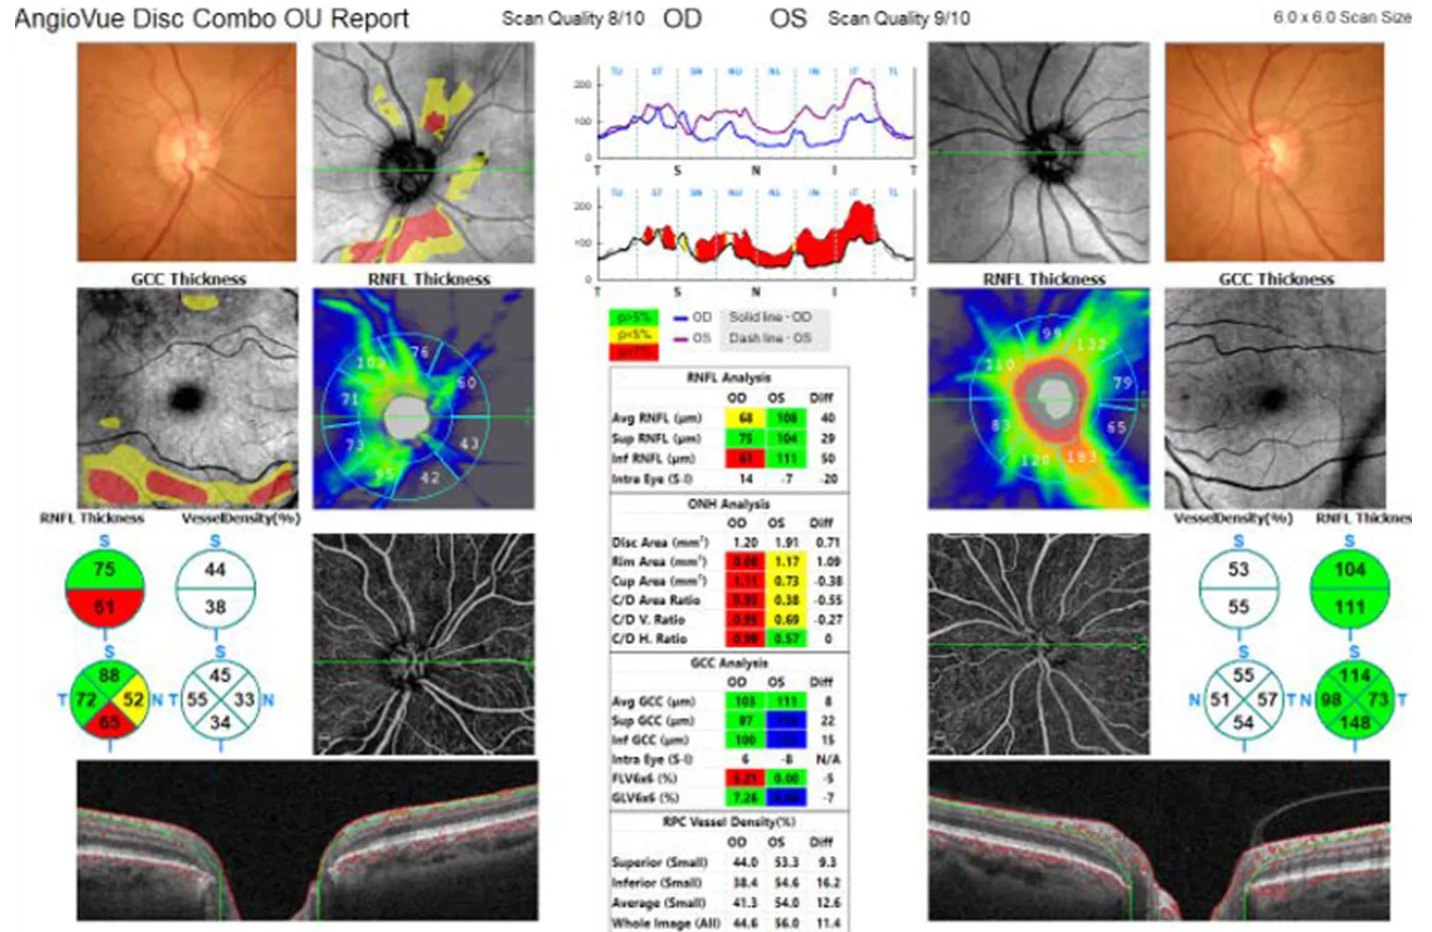

Оптический когерентный томограф Optovue Solix обладает повышенной скоростью сканирования — 120 000 А-сканов в секунду. SOLIX предоставляет множество инструментов для нового поколения борьбы с заболеваниями, которые повышают пропускную способность и обеспечивают превосходный уход за пациентами. В отличие от томографов более ранних поколений ОКТ SOLIX OPTOVUЕ может определять наличие конкрементов и новообразований сосудов сетчатки и хориоидеи, позволяет получать максимально точную послойную визуализацию структур глаза.

- Диапазон сканирования в режиме ангио-ОКТ — от 3х3 до 18х18 мм;

- Программа AngioAnaliticsTM для количественного анализа сосудов сетчатки;